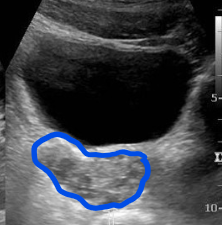

7. Cystic Lesions 30%

Congenital Seminal Vesicle Cysts

Acquired Retention Cysts

Simple vs Complex Appearance

Differentiation from Mullerian Duct or Ejaculatory Duct Cysts